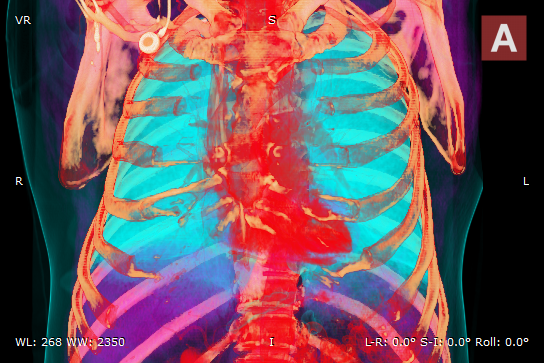

Angio